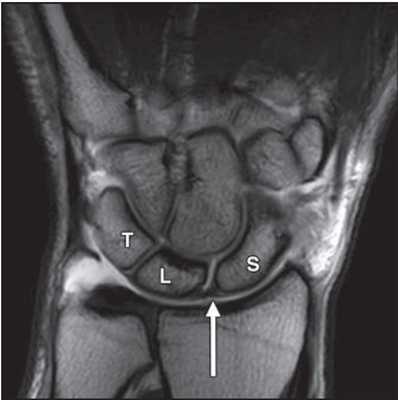

МРТ кисти. Корональная Т1-взвешенная МРТ. Нормальное изображение ладьевидно-полулунной связки. Обозначения: S – ладьевидная кость (scaphoid), L – полулунная кость (lunatum), T- трехгранная кость (triquetrum).